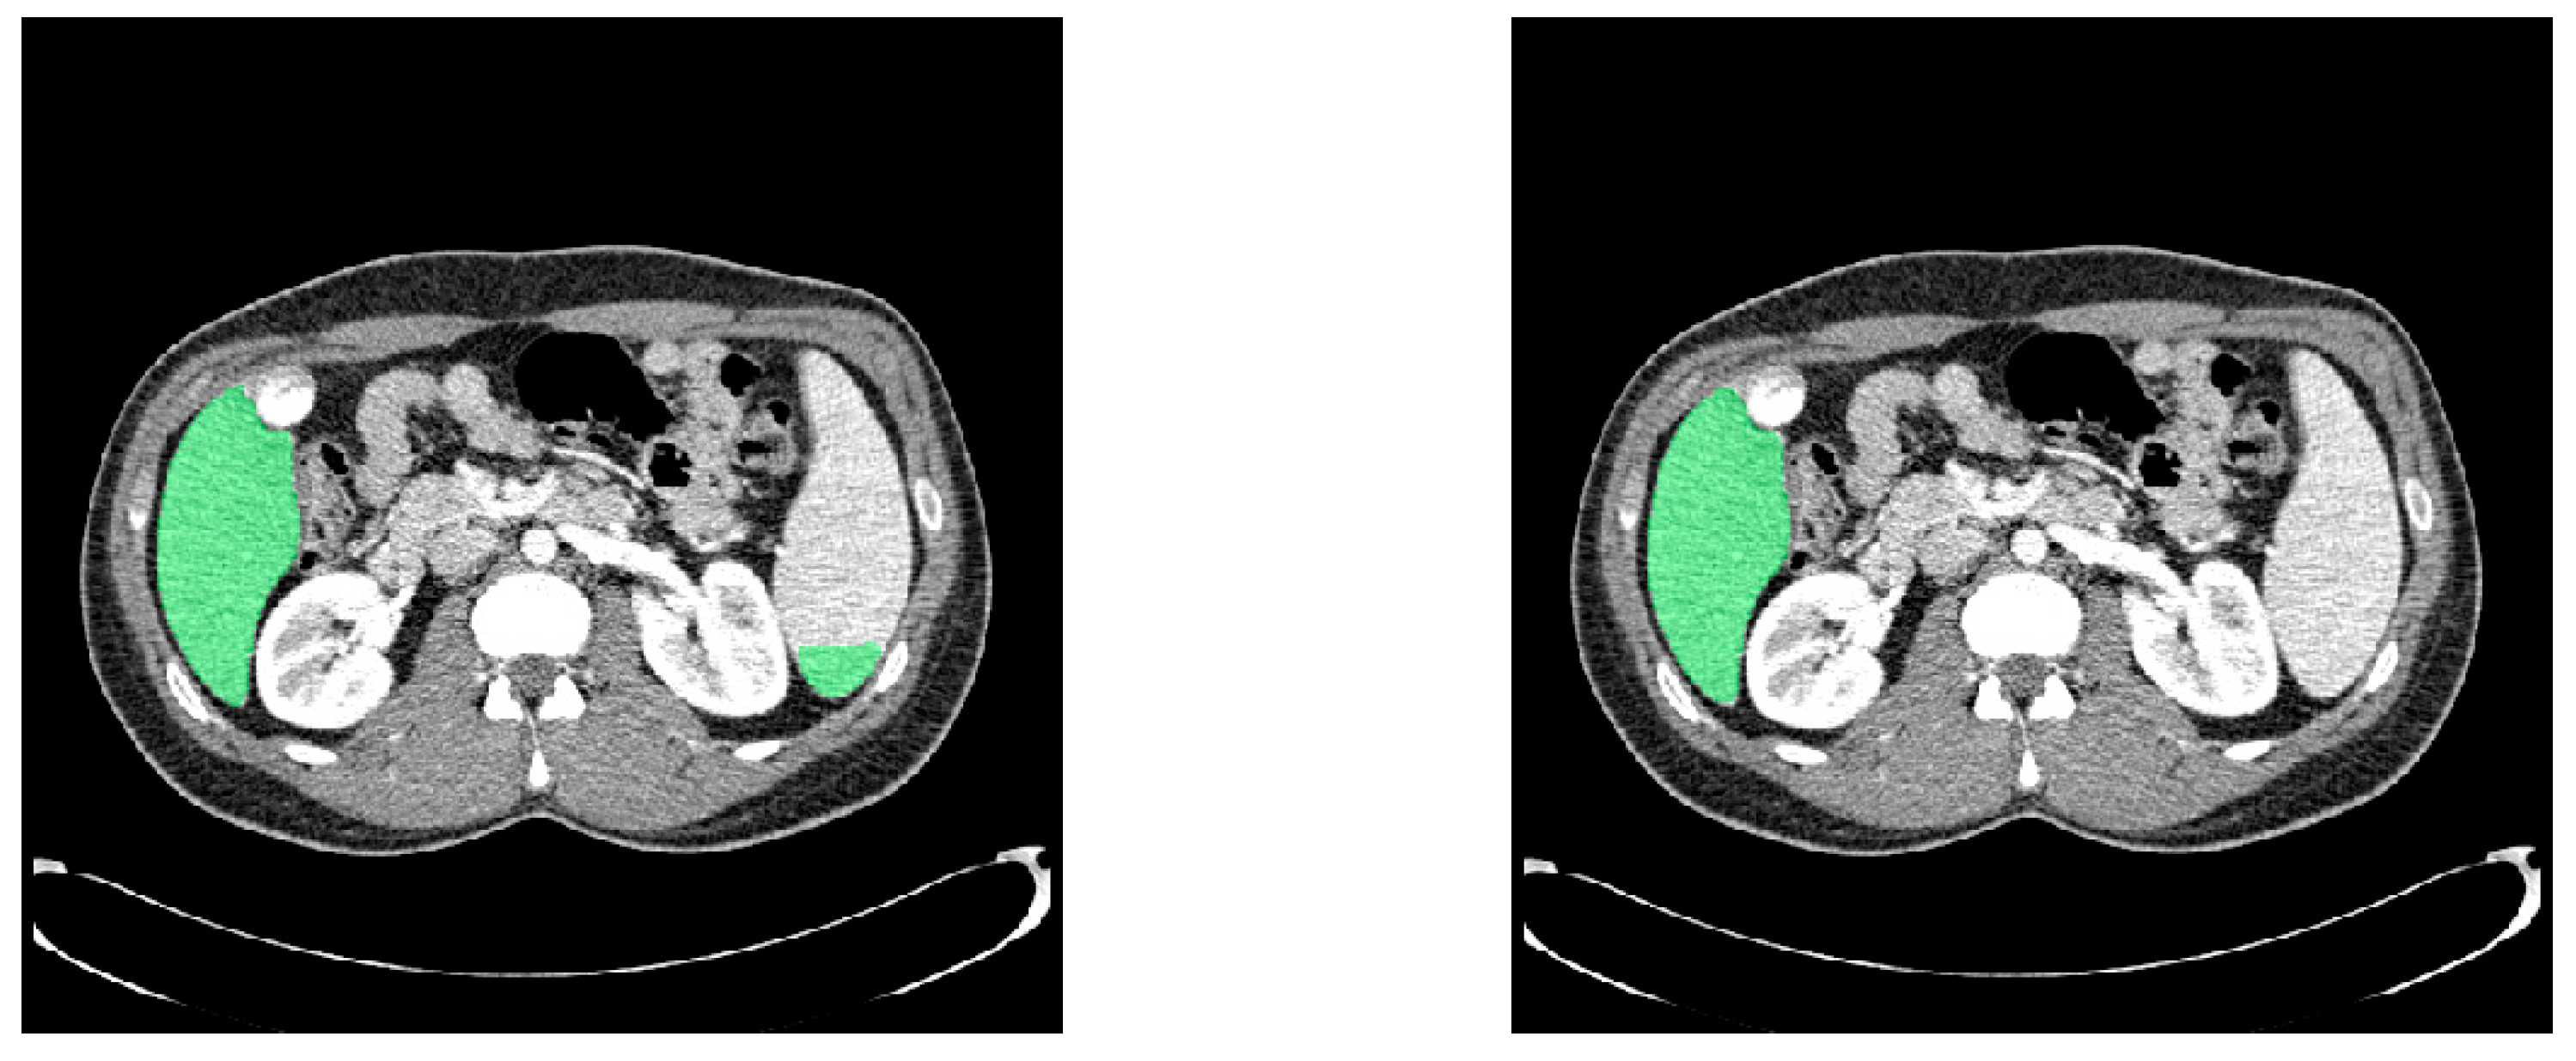

4.3. Post-Processing